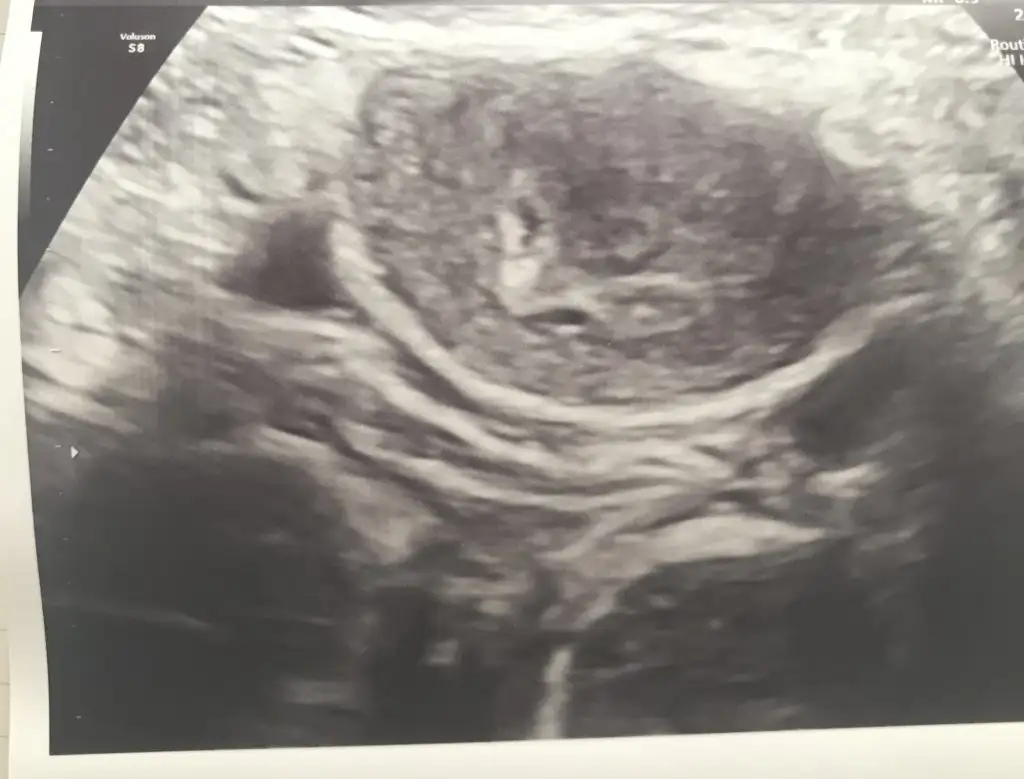

5 ve 14. haftaya kadar olan ultrason fotolarınızı paylaşın. Vajinadan mı yoksa karından mı çekildiğini ve kaç haftalık olduğunu da mutlaka belirtin.